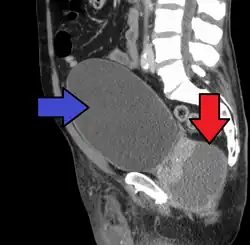

Severely ill patients may need hospitalization, while nontoxic patients can be treated at home with bed rest, analgesics, stool softeners, and hydration. Men with acute prostatitis complicated by urinary retention are best managed with a suprapubic catheter or intermittent catheterization. Lack of clinical response to antibiotics should raise the suspicion of an abscess and prompt an imaging study such as a transrectal ultrasound (TRUS).[7]